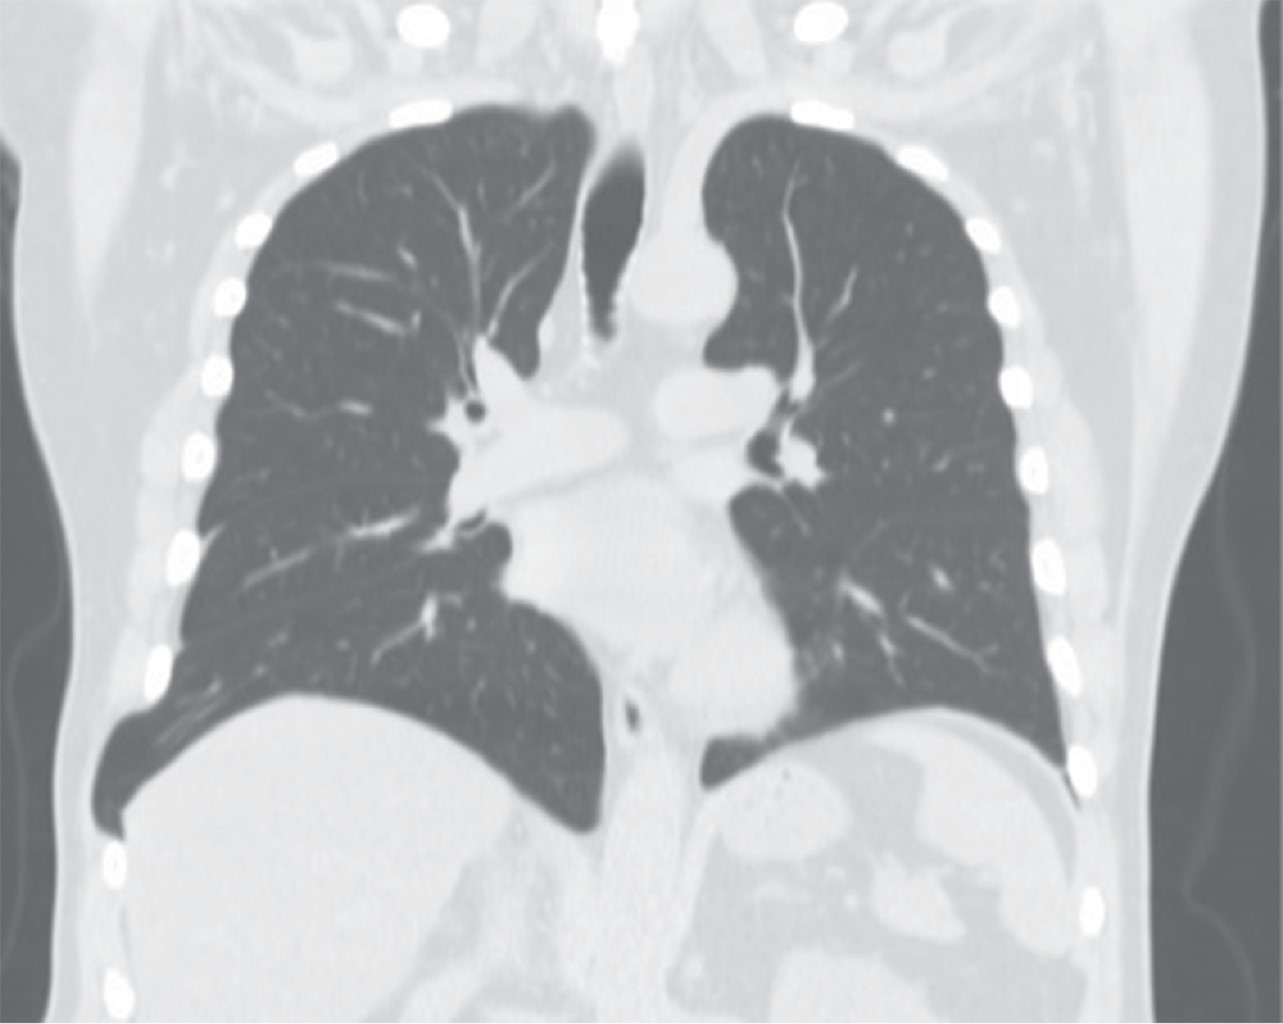

Thoraco-laparoscopic management of an acquired abdominal intercostal hernia

Abdominal intercostal hernias are a rare condition, characterized by the protrusion of the content of a hernia through an intercostal defect without diaphragmatic abnormalities. Most occur in the context of trauma and associated rib fractures. We present the case of a patient whose hernia was only associated with a chronic cough without a costal fracture. We describe a different form with a mixed approach to abdominal and chest reinforcement for minimal invasion.

Figure 1